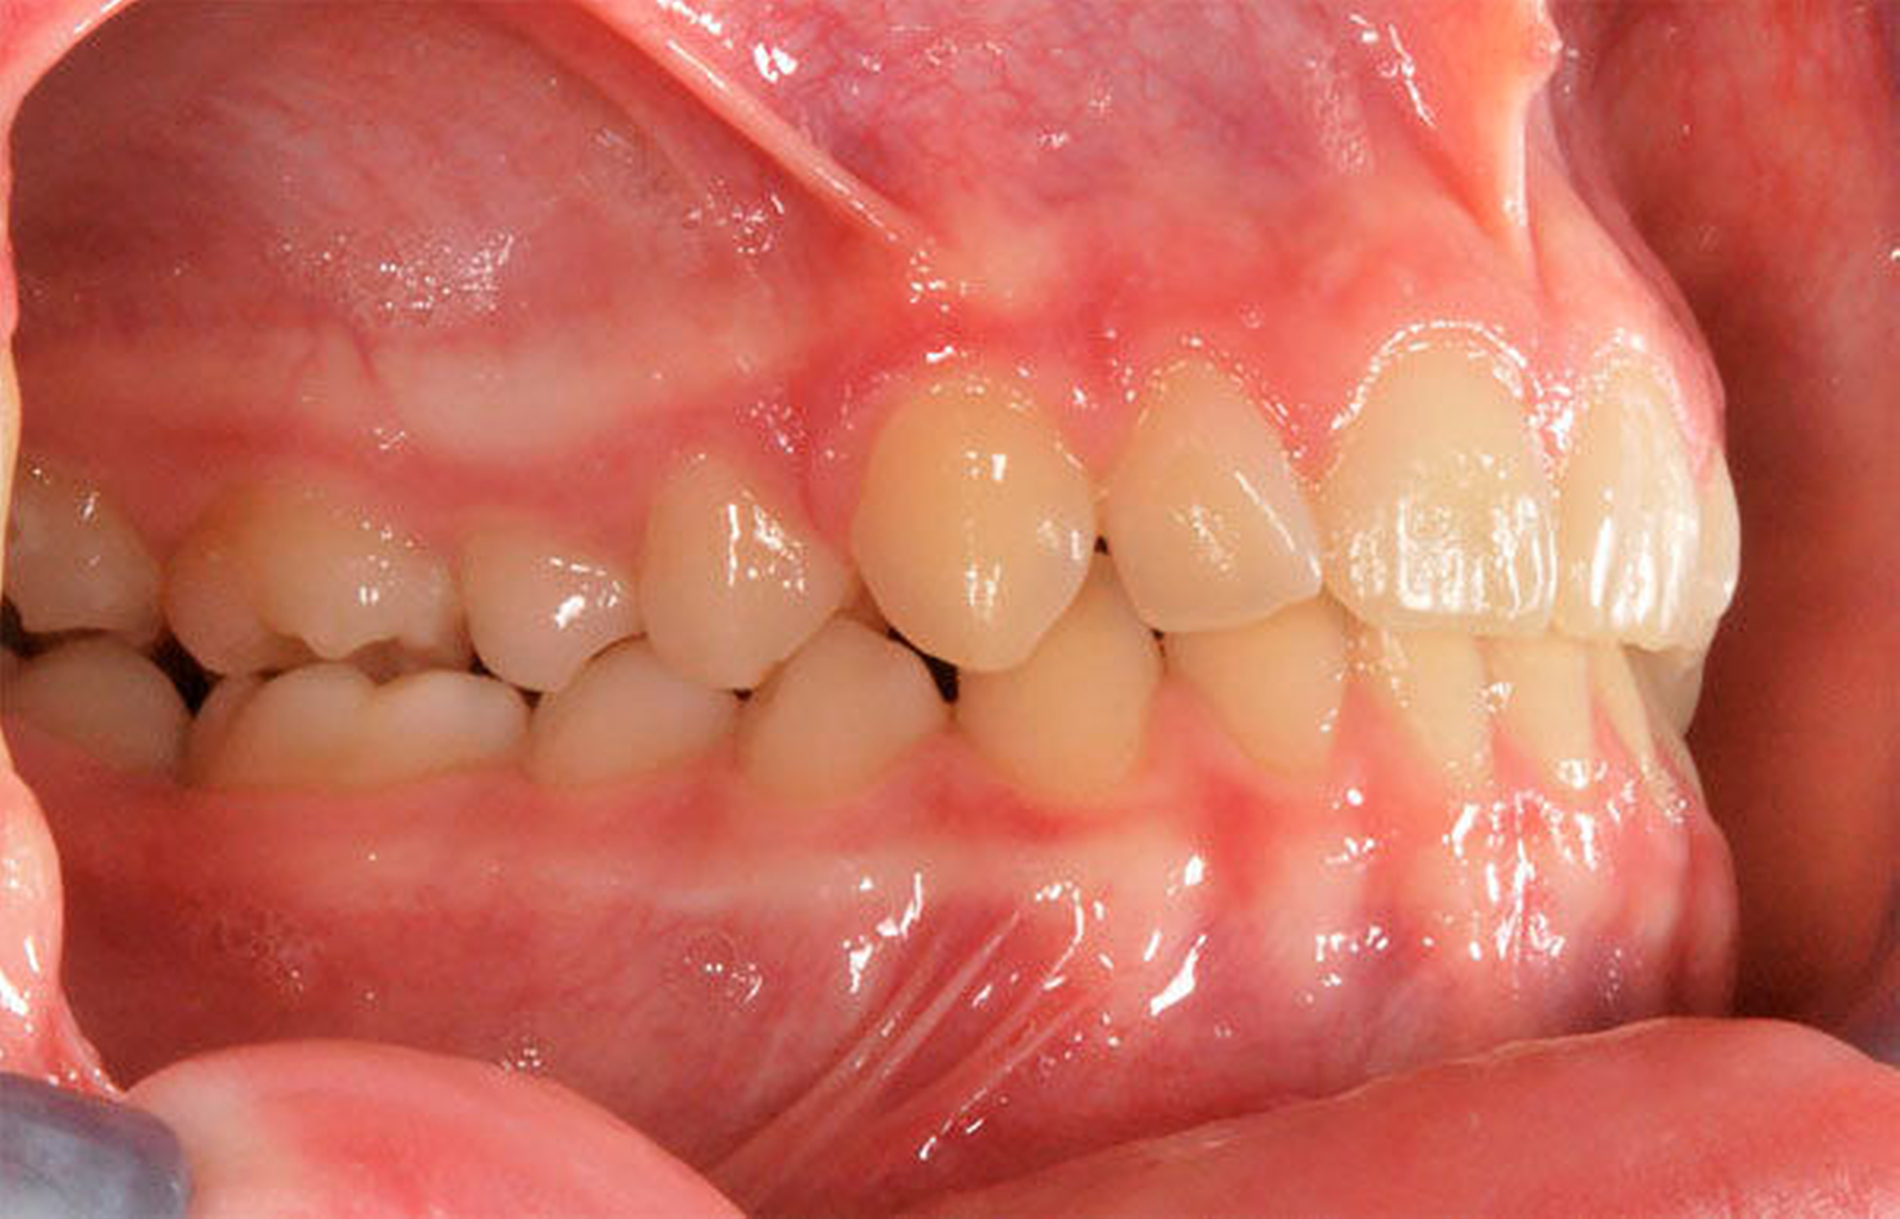

Besonders wichtig ist aus zahnärztlich-kieferorthopädischer Sicht die Beurteilung der lateralen Okklusionsverhältnisse [Kahl-Nieke, 2015]. Der unilaterale Kreuzbiss kommt ungefähr viermal häufiger vor als der bilaterale [Schopf, 2003]. Bei 80 Prozent der Kinder mit einseitigem Kreuzbiss tritt eine funktionelle Unterkieferabweichung auf [Kurol, 1992] und die Unterkiefermitte verschiebt sich dabei zur Kreuzbissseite [Santos Pinto, 2001] bei gleichzeitig asymmetrischer Kondylenposition. Diese reflektorische Einnahme der Kreuzbissstellung vergrößert die Anzahl der Okklusionskontakte, mit der Gefahr, dass nach kurzer Zeit diese transversale Fehlstellung des Unterkiefers neuromuskulär fixiert wird. Bei Belassen des Kreuzbisses kann eine skelettale Manifestation der Asymmetrie und eine dauerhafte Abweichung der Kinnmitte von der Gesichtsmitte resultieren [Hesse, 1997; O`byrn, 1995]. Erfolgt keine frühzeitige Therapie, besteht zudem die Gefahr einer Wachstumshemmung im Bereich der im Kreuzbiss „eingefangenen“ Oberkieferseite. Eine kieferorthopädische Frühbehandlung scheint präventiv gegen eine skelettale Adaptation und gegen eine Persistenz des Kreuzbisses in die permanente Dentition zu wirken [Harrison, 2001]. Das Überstellen des lateralen Kreuzbisses durch transversale Weitung des Oberkiefers kann beispielsweise mittels forcierter Gaumennahterweiterung [Köbel, 2017] erfolgen und wirkt sich neben einer Verbesserung der respiratorischen Situation günstig auf die Beseitigung skelettaler und dentoalveolärer Asymmetrien aus [Hesse, 1997; Santos Pinto, 2001] (Abbildung 3).